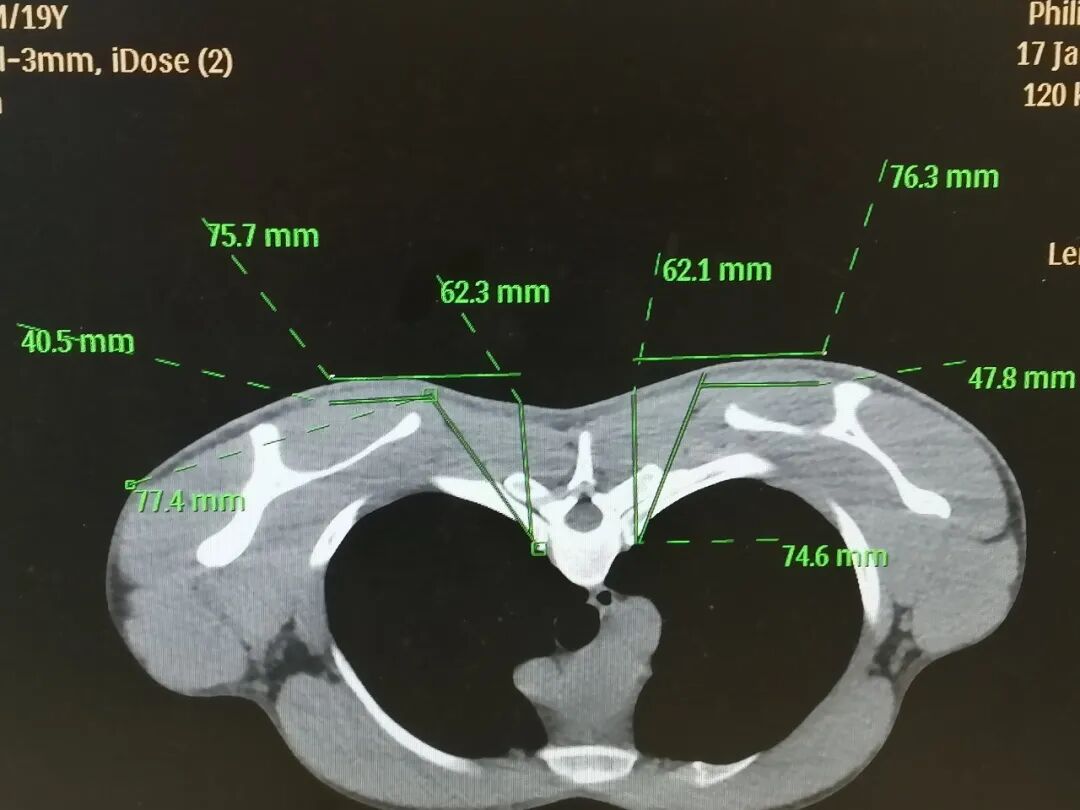

2026年1月17日,江门市中心医院疼痛科黄俊伟主任团队成功为小林实施了CT引导下双侧胸交感神经链射频损毁术。这标志着一项针对重度手汗症等顽疾的精准微创治疗技术,正式在我院落地生根,为长期受交感神经功能紊乱困扰的患者,点亮了一盏希望之灯。

在经过保守治疗及严谨的术前评估后,我院疼痛科黄俊伟主任医疗团队决定为小林施行创伤及对身体影响最小的的CT引导下胸交感神经链射频损毁术。与传统手术相比,该技术无需气管插管全身麻醉,创伤极小,仅在背部穿刺两个针眼。

CT术前精准测绘定位

术中,在CT影像的实时精确引导下,手术团队犹如拥有了“透视眼”,将射频穿刺针安全、准确地送达目标胸交感神经链。随后,通过可控的温度对过度亢奋的交感神经进行精准调控。在温控热凝的过程中,小林明显感觉到双侧手掌的温度逐渐升高;术后约10分钟,小林手掌的多汗症状便神奇地消失了。触摸着自己干燥温暖的双手,积压十余年的情绪瞬间释放,才有了手术台上那感人至深的一幕。